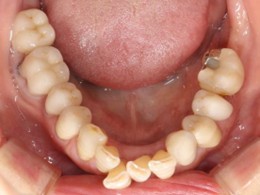

50代 男性

治療前

治療後

治療後- 年齢/性別

- 50代/男性

- 主訴

- 上顎の義歯の具合が悪いため、インプラント希望

- 治療期間

- 1年間

- 治療費

- インプラント¥4,400,000

骨造成¥220,000

サージカルステント¥99,000 - リスク・副作用

- 術後の腫れ・出血